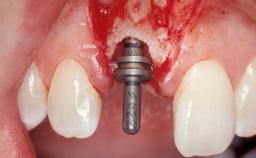

Late Placement of an Implant in a Maxillary Left Central Incisor Site

Type of Implants Two-Piece

Bone Augmentation Horizontal|Staged

Augmentation Materials Xenogenous|Membrane

Bone Volume Deficient horizontally, requiring prior grafting